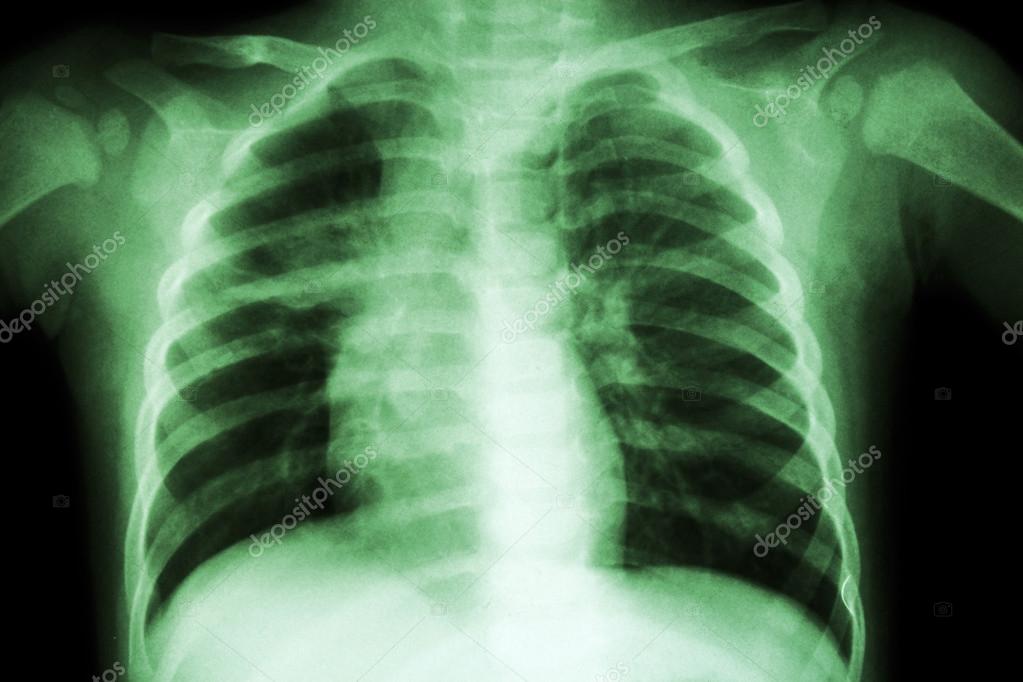

Ct of the thorax is feasible if: And some patients may show symptoms of cervical lymphadenectasis. The article reviews the imaging findings in ctb on various modalities. The typical image is a homogeneous or heterogeneous white spot at the base of the affected lung or the middle third. It may be a primary tuberculous infection, secondary infection or appear as chronic scarring. Mri allows for the rapid determination of the mechanism for neurologic involvement. This helps your doctor choose the medications that are most likely to work. For decades, tuberculosis (tb), a potentially serious infectious lung disease, continues to be a leading cause of worldwide death.

In postprimary tuberculosis, the most common imaging findings include cavitary lesions in which patients present with fever, night sweats, weight loss, and cough. A general discussion of tuberculosis is found in the parent article: The typical image is a homogeneous or heterogeneous white spot at the base of the affected lung or the middle third. Mri is the neuroimaging of choice for spinal tuberculosis. This helps your doctor choose the medications that are most likely to work.